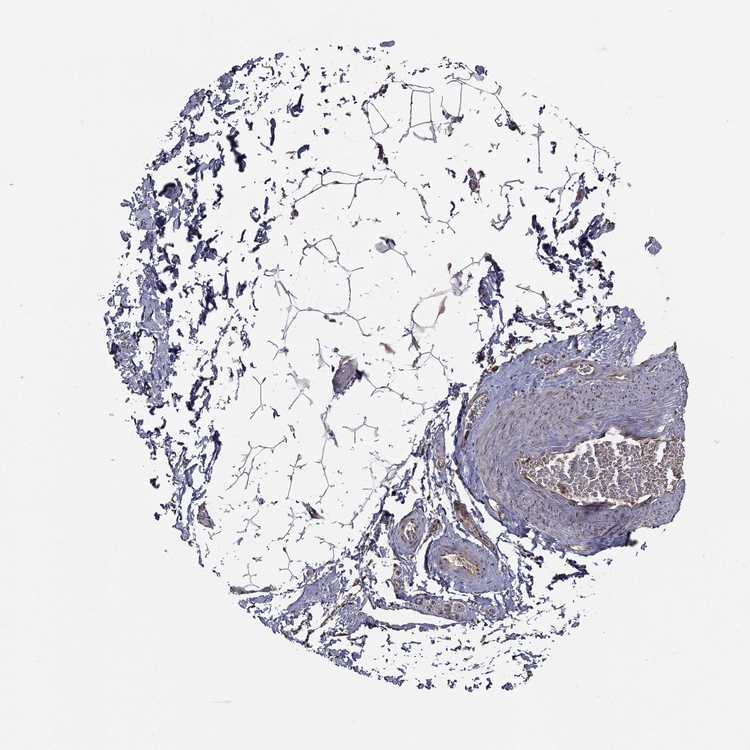

SOFT TISSUE 1 - Antibody stainingi

Antibody staining in the annotated cell types in the current human tissue is reported as not detected, low, medium, or high, based on conventional immunohistochemistry profiling in selected tissues. This score is based on the combination of the staining intensity and fraction of stained cells.

Each image is clickable and will lead to virtual microscopy that enables deeper exploration of all samples and also displays staining intensity scores, fraction scores and subcellular localization as well as patient and tissue information for each sample.

Antibody HPA064901

Fibroblasts Not detected

Peripheral nerve Not detected

SOFT TISSUE 2 - Antibody stainingi